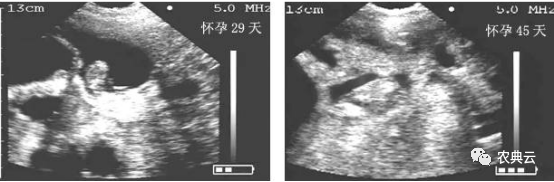

1. 第一时间检测出是否怀孕(第一个发情期之后,一般在24-29天)应该讲在这个阶段检测出有无怀孕,对于养殖场来说是最省钱的,如果空怀可以及时再配,从而大大缩短了无效饲养的时间。早期估测出来胚胎个数,有利于妊娠母猪日粮中营养配方以及饲喂量的调整。当胚胎个数较多而营养和日粮跟不上时,容易造成流产或弱胎;而当胚胎个数较少而营养和日粮过剩时,容易造成胚胎个体发育过大,引起难产。